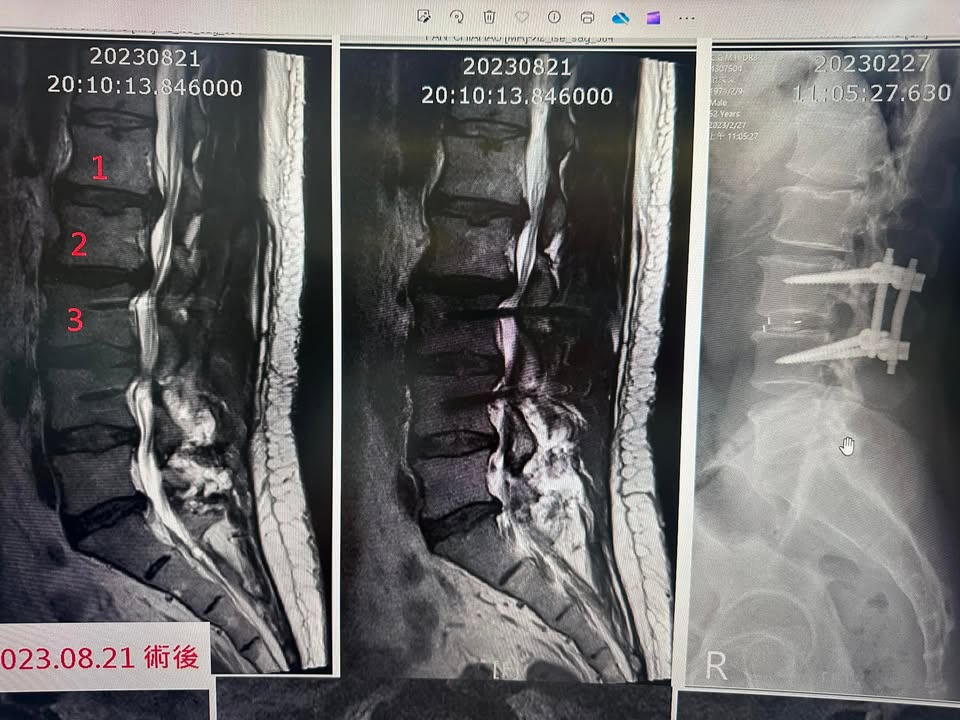

Cervical Spine Treatment Cases 精彩回顧 2024.09.06 2024.09.09 做完腰椎融合手術打了六支釘子之後嚴重惡化 2024.09.11 椎弓解離骨折導致滑脫一定要開刀嗎 2024.09.15 脊椎手術後嚴重沾黏案例 2024.09.18 又是脊椎手術後遺症沾黏 2024.09.20 脊客救援俠醫出任務 2024.09.21 2024.09.21 2024.09.24 2024.09.26 2024.09.26 2024.09.29 2024.10.02 颱風天必須提到這首歌六年級五年級才懂 2024.10.03 2024.10.04 ← 上一頁 22 23 24 25 26 下一頁 →